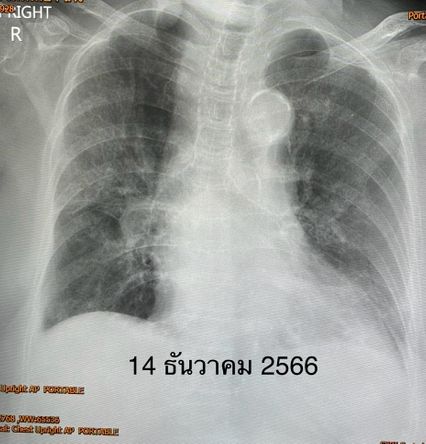

หมอมนูญได้ยกเคสผู้ป่วยหญิง อายุ 95 ปี เคยป่วยเป็นมะเร็งต่อมน้ำเหลืองเมื่อ 5 ปีก่อน รักษาหายแล้ว มีโรคประจำตัวเป็นโรคความดัน ไม่เคยติดเชื้อโควิด และไม่เคยฉีดวัคซีนป้องกันโรคโควิดแม้แต่เข็มเดียว ต่อมาพบว่ามีไข้ ไอมีเสมหะ เหนื่อย ระดับออกซิเจนที่ปลายนิ้วต่ำ 89% ตรวจ ATK ให้ผลบวก เอกซเรย์ปอดมีฝ้าขาวทั้ง 2 ข้าง

แพทย์วินิจฉัยว่า ปอดอักเสบจากไวรัสโควิด-19 ให้เข้านอนรักษาในโรงพยาบาล เมื่อวันที่ 14 ธ.ค.66 ให้ออกซิเจน 6 ลิตร/นาที ให้ยาฉีดเรมเดซิเวียร์และยากินแพ็กซ์โลวิดพร้อมกัน 5 วัน และยาสเตียรอยด์ คนไข้ดีขึ้นช้าๆ แพทย์ให้กลับบ้านได้ในวันที่ 24 ธ.ค.66 (รักษานาน 10 วัน) หลังกลับบ้านเพียง 1 วัน ผู้ป่วยมีอาการเหนื่อย และมีไข้ขึ้นอีก ตรวจ ATK ให้ผลลบ แต่ผลส่งตรวจรหัสพันธุกรรมยังพบไวรัสโควิด-19 เอกซเรย์ปอดมีฝ้าขาวเพิ่มขึ้น และปอดขนาดเล็กลง